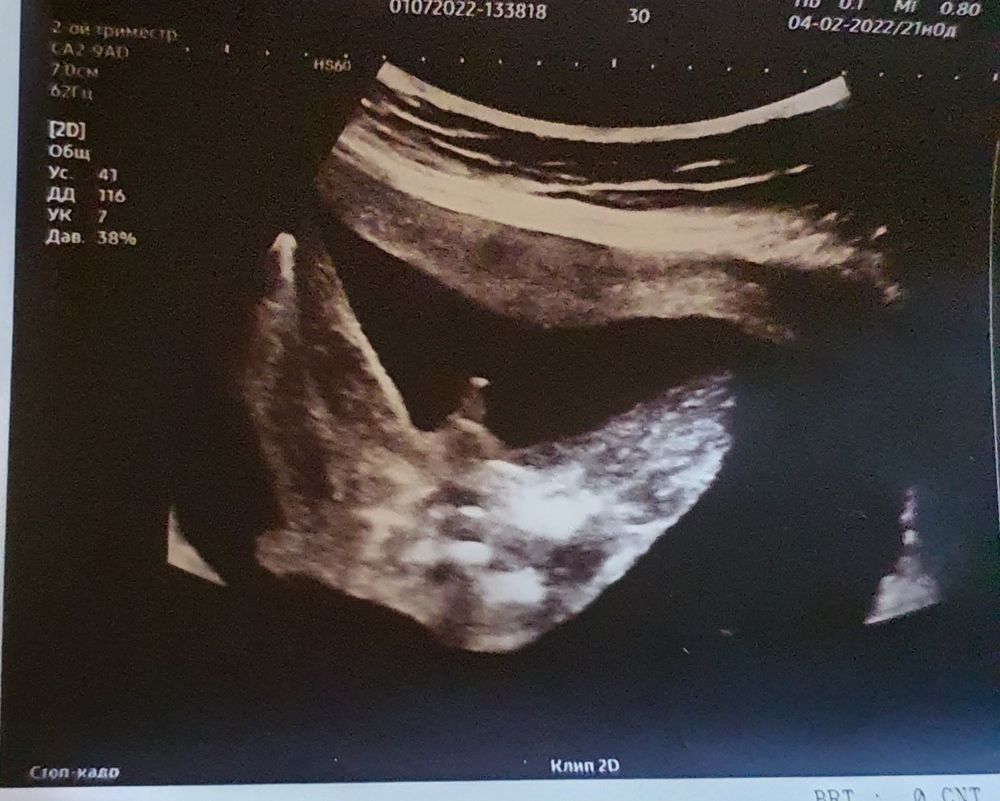

У меня два замечательных сына, сейчас в ожидании чуда 🤰

на первом узи в 12 недель врач сказал у вас девочка (но конечно верить не могу на первом узи, так как в 12году с сыном до 3 скрининга говорила девочка, а со вторым в принципе все время говорили мальчик, один раз не поняли кто 😅)

на втором узи в 20 недель врач дал конверт в котором было написан